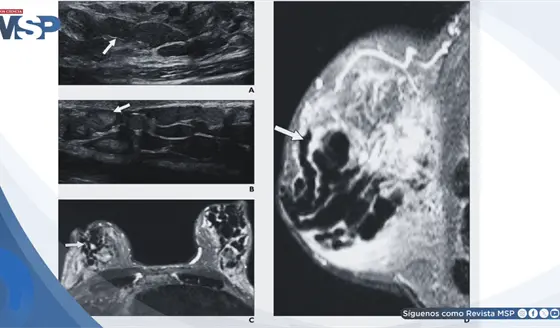

Galactorrea, secreción mamaria y aumento de prolactina generado por efecto adverso de metoclopramida